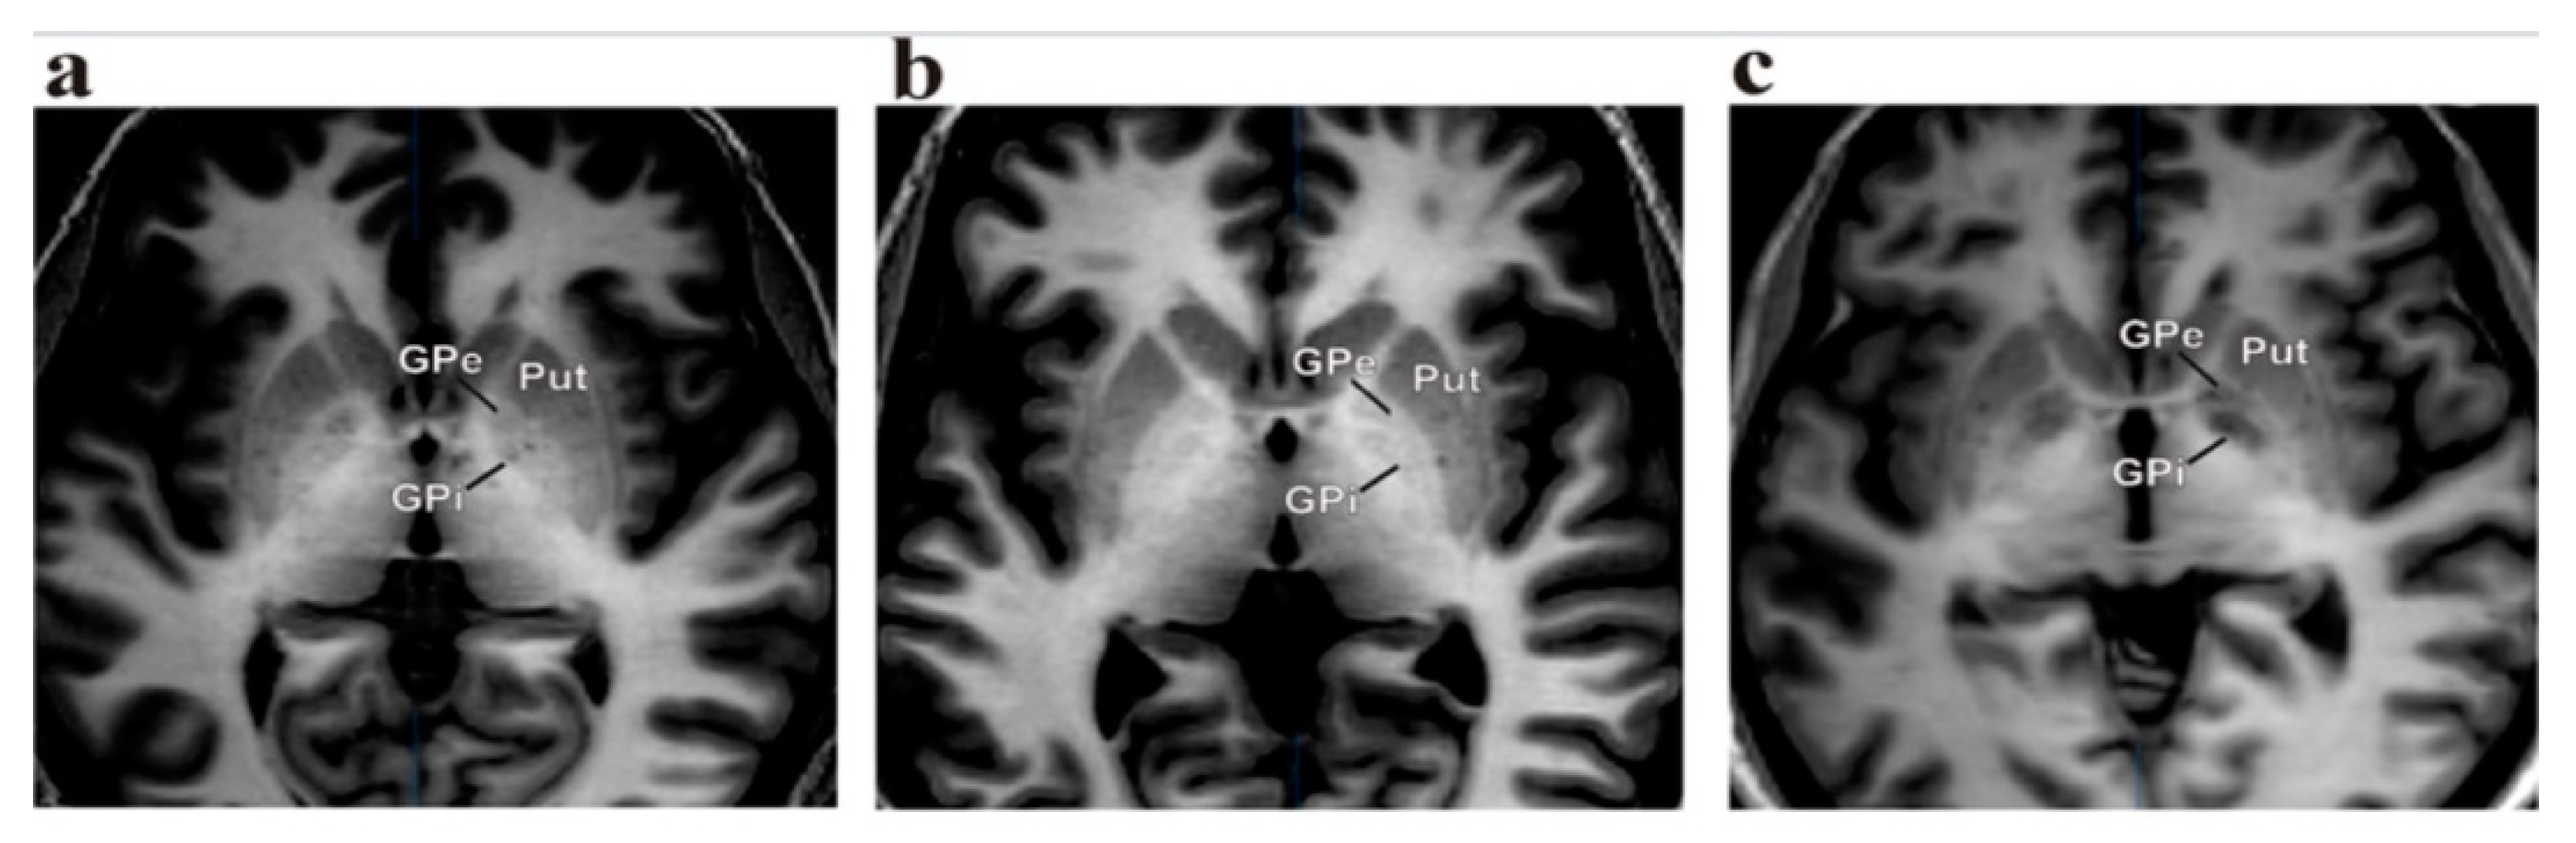

2.4. Operative Technique